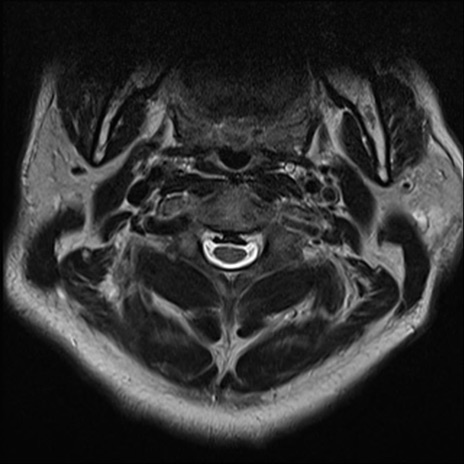

【整形】TIPS症例7 頚椎MRI T2WI(横断像)

頚椎MRI

矢状断像と横断像